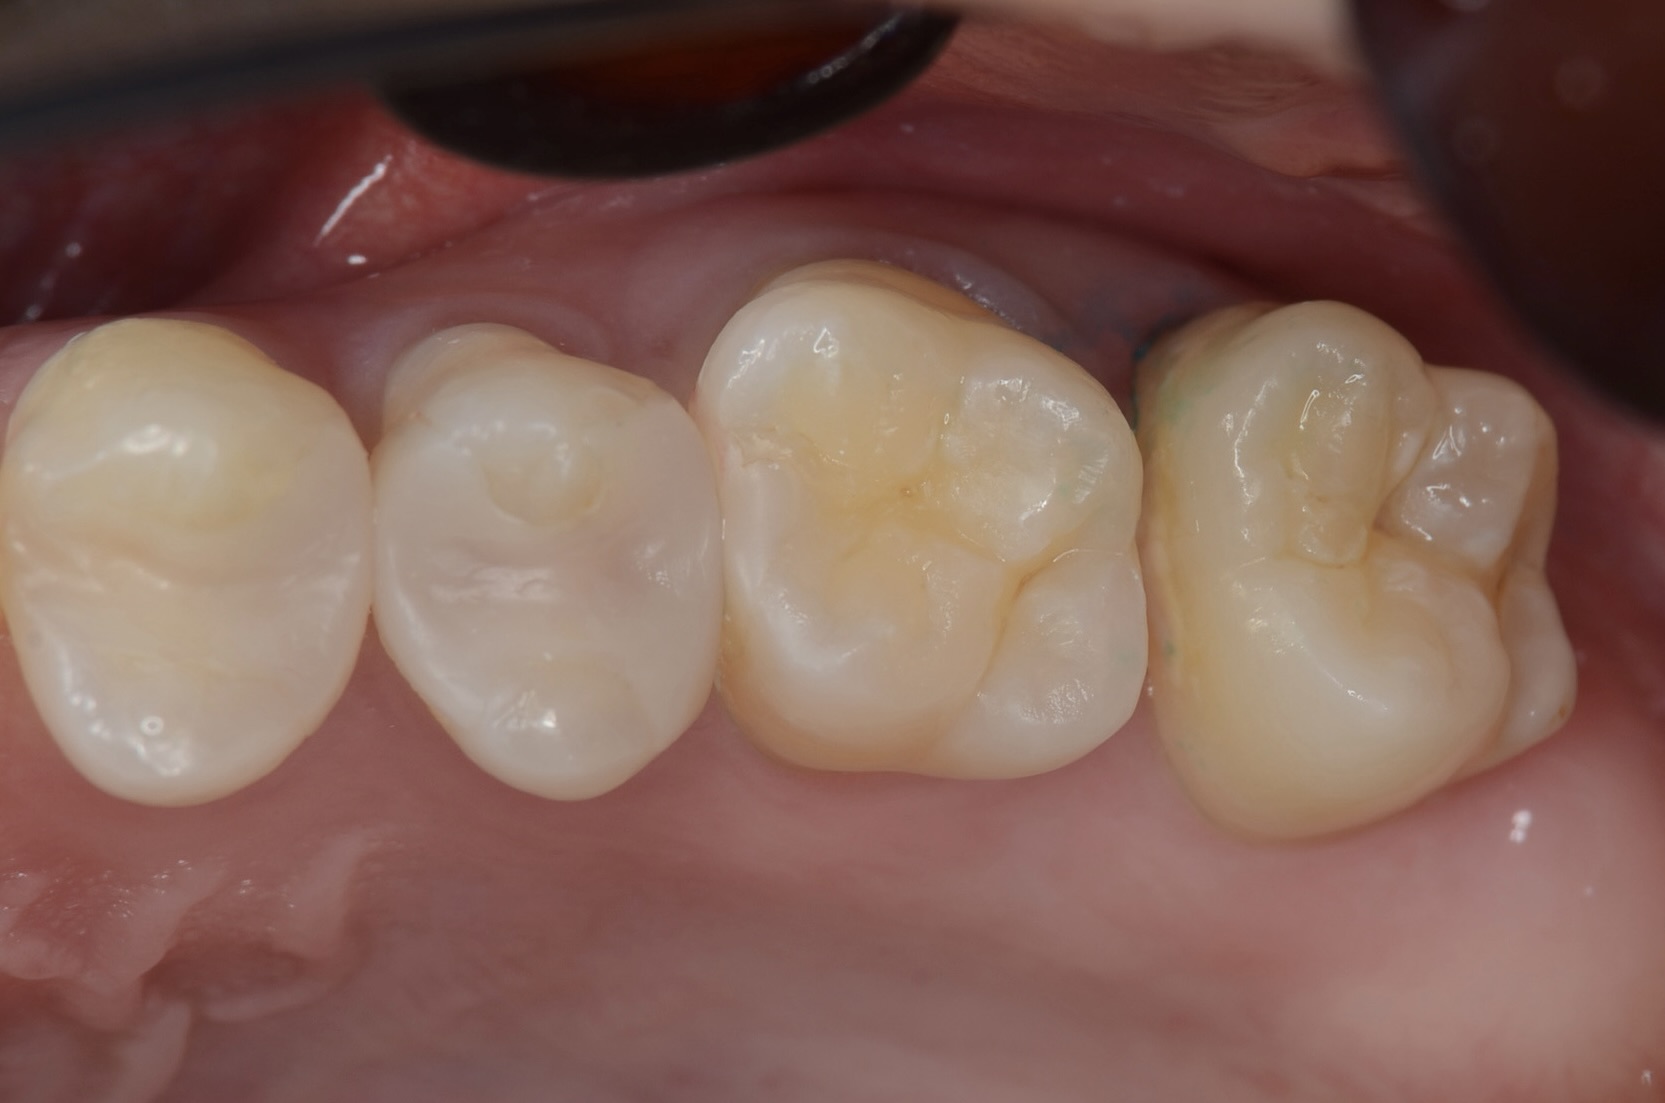

口蓋側面観

手間はかかりますがこれによって、隙間から治療することで、歯を削る量を減らします。 -

7番近心

初期虫歯に見えますが削ると中で虫歯が広がっています。 -

6番遠心の虫歯

-

完全虫歯を除去しました -

7番近心にダイレクトボンディング

1週間後

広がった歯間が自然に閉じています。